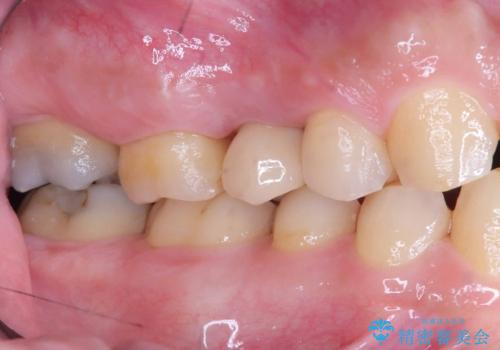

右上5番が根尖性歯周炎と歯周病が同時に併発しており、骨が大きく溶け、歯の動揺も著しかったため保存困難と判断をし抜歯してインプラントで治療を行いました。

インプラントはインプラント周囲炎になりにくいスクリュータイプを使用しています。

右上4番は虫歯になっていたので、虫歯を除去後、セラッミクインレーで治療を行いました。

- 税込814,000円(インプラント10年保障297,000円+カスタムアバットメント110,000円+オールセラミッククラウンエクセレント220,000円+骨造成55,000円+セラミックインレー77,000円act)費用は治療当時の料金となります